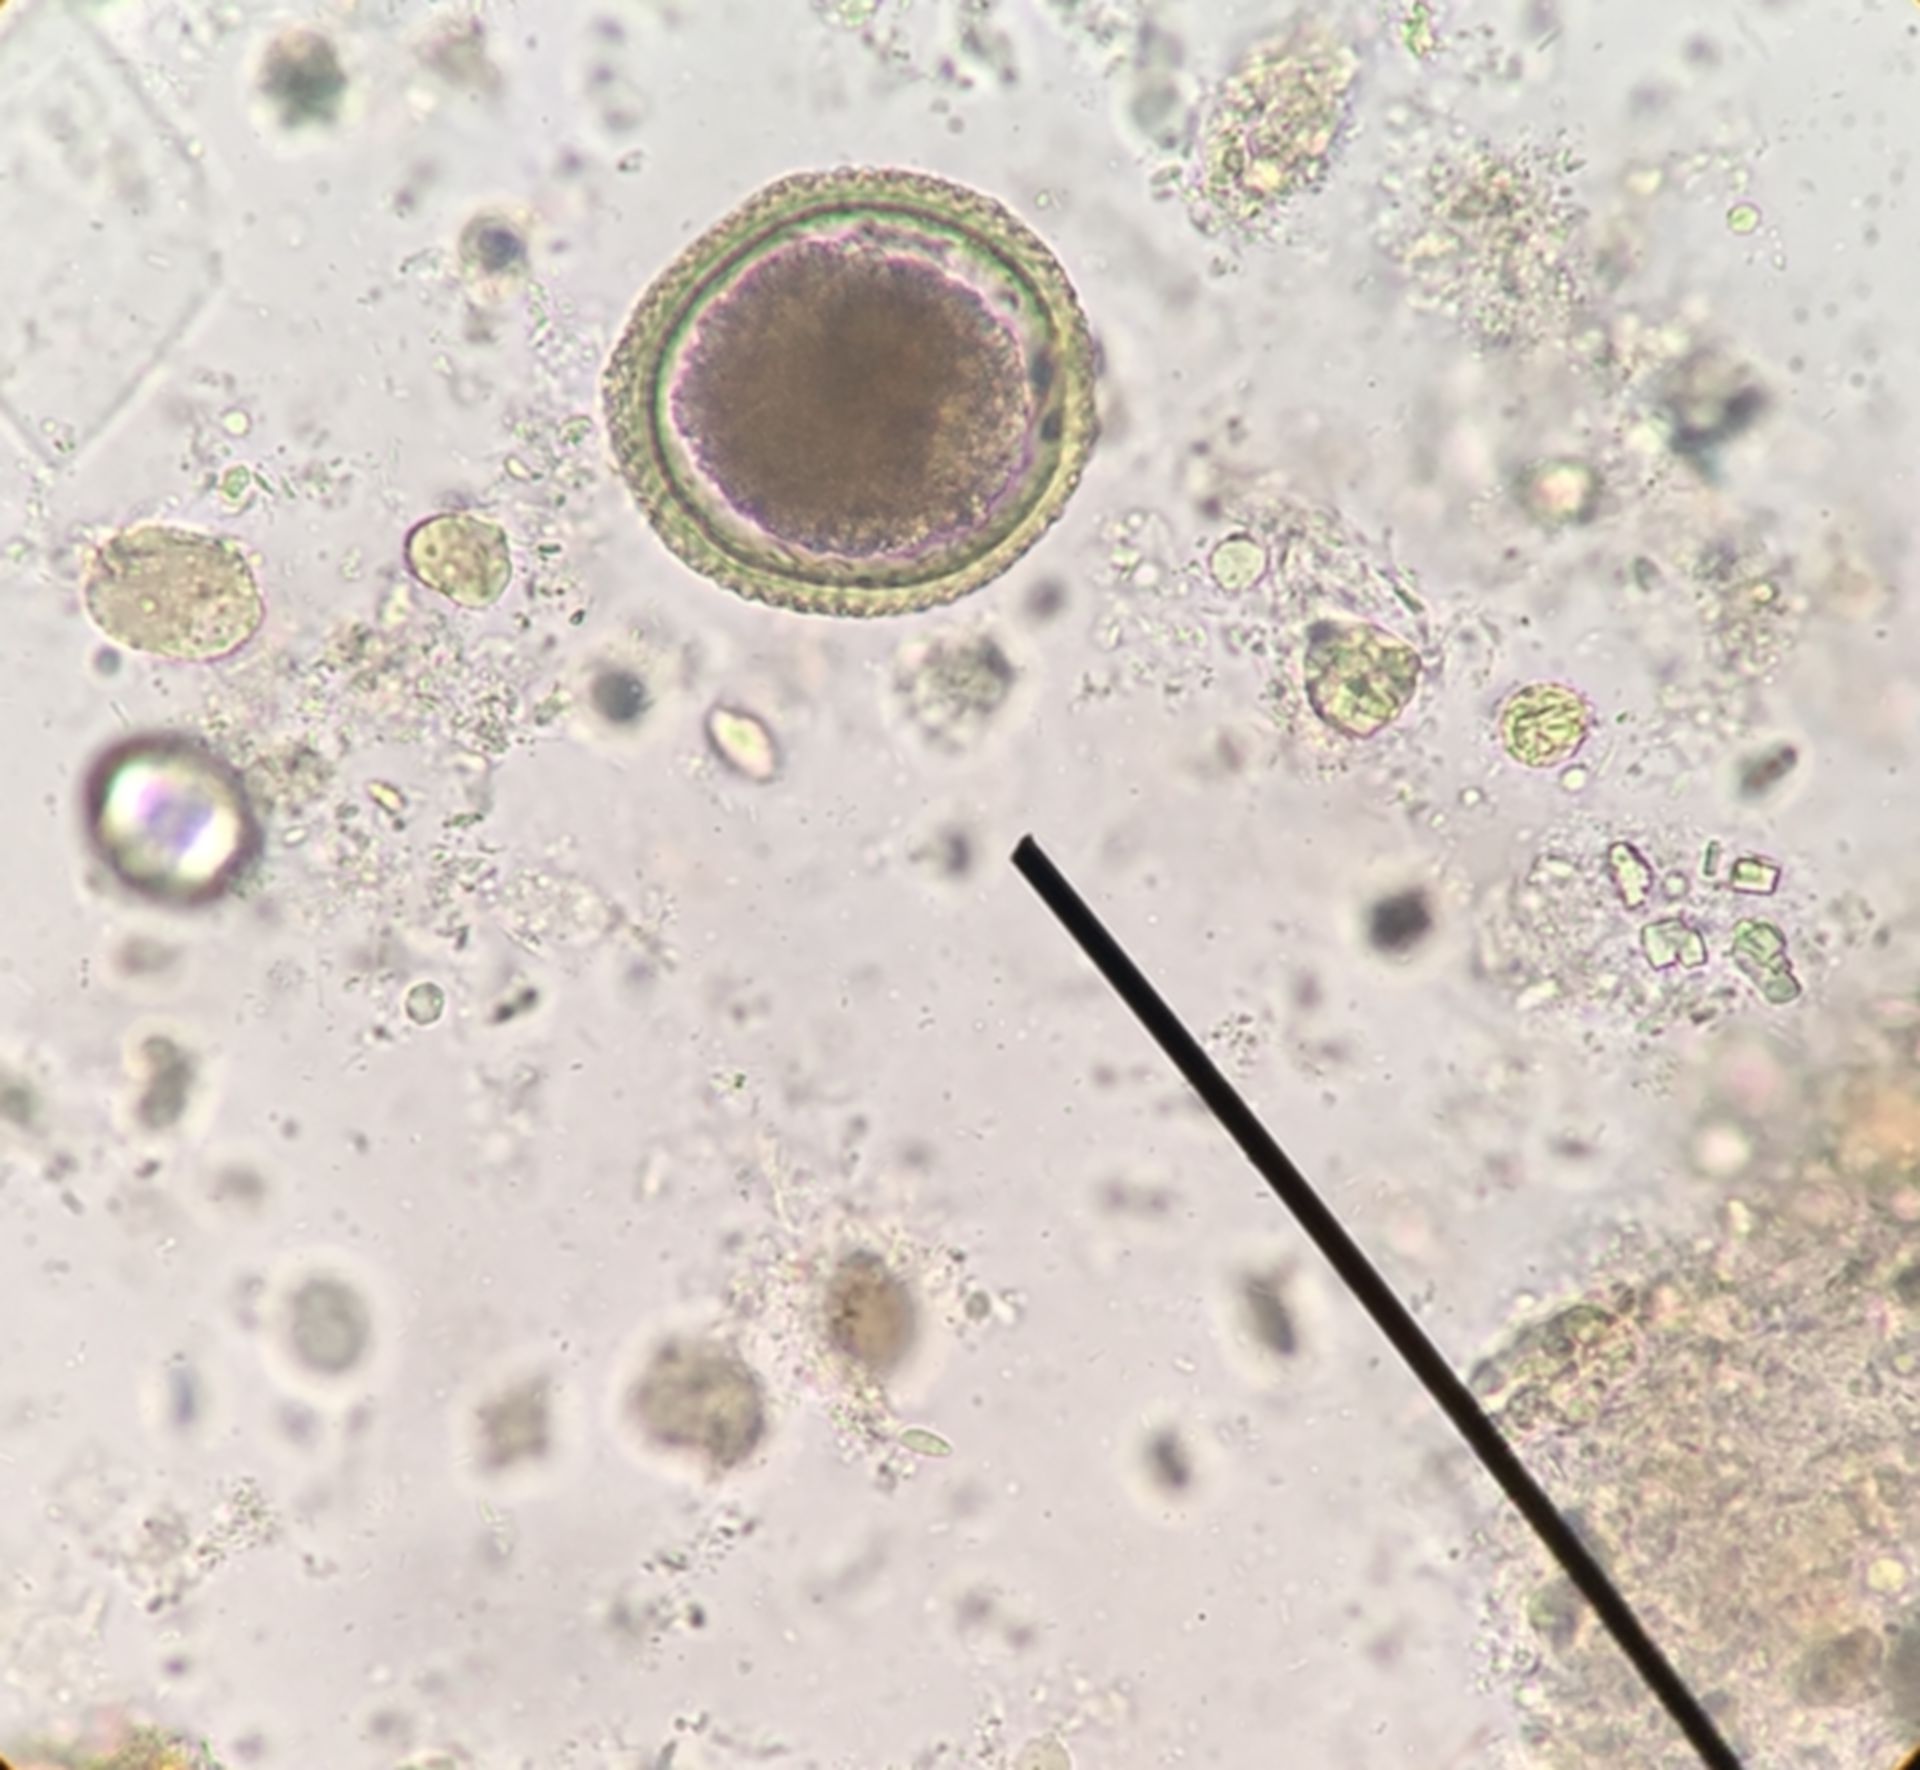

Микрофотографии яиц гельминтов Toxocara canis

Раздел: Фотоэссе